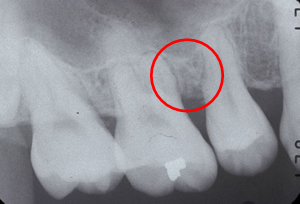

治療後のエックス線像、骨が再生されました。 |